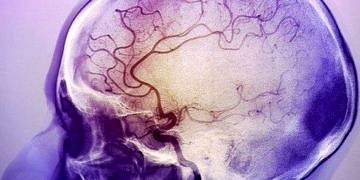

İnsanların konuşma, hareket etme, görme, duyma gibi temel fonksiyonlarını yerine getirmek için gereken enerjiyi, beyine atardamarlar taşır. İnme olarak adlandırılan...

Önlem alınmadığı takdirde kişide hayati risk ve kalıcı sakatlıklara yol açan inme, yaşam tarzında yapılacak değişiklikler ve düzenli sağlık kontrolleri...

Dünyada yılda 15 milyon kişi, Türkiye’de ise her yıl 130 bin kişi inme ya da felç geçiriyor. İnmede en büyük risk faktörleri arasında sigara kullanımı, hipertansiyon ve...

DevamıTüm dünyada bir yılda 17 milyon kişi inme geçiriyor ve 6 milyon kişi de bu hastalık nedeniyle hayatını kaybediyor. Üstelik görülme sıklığı 50 yaş ve sonrasında artsa...